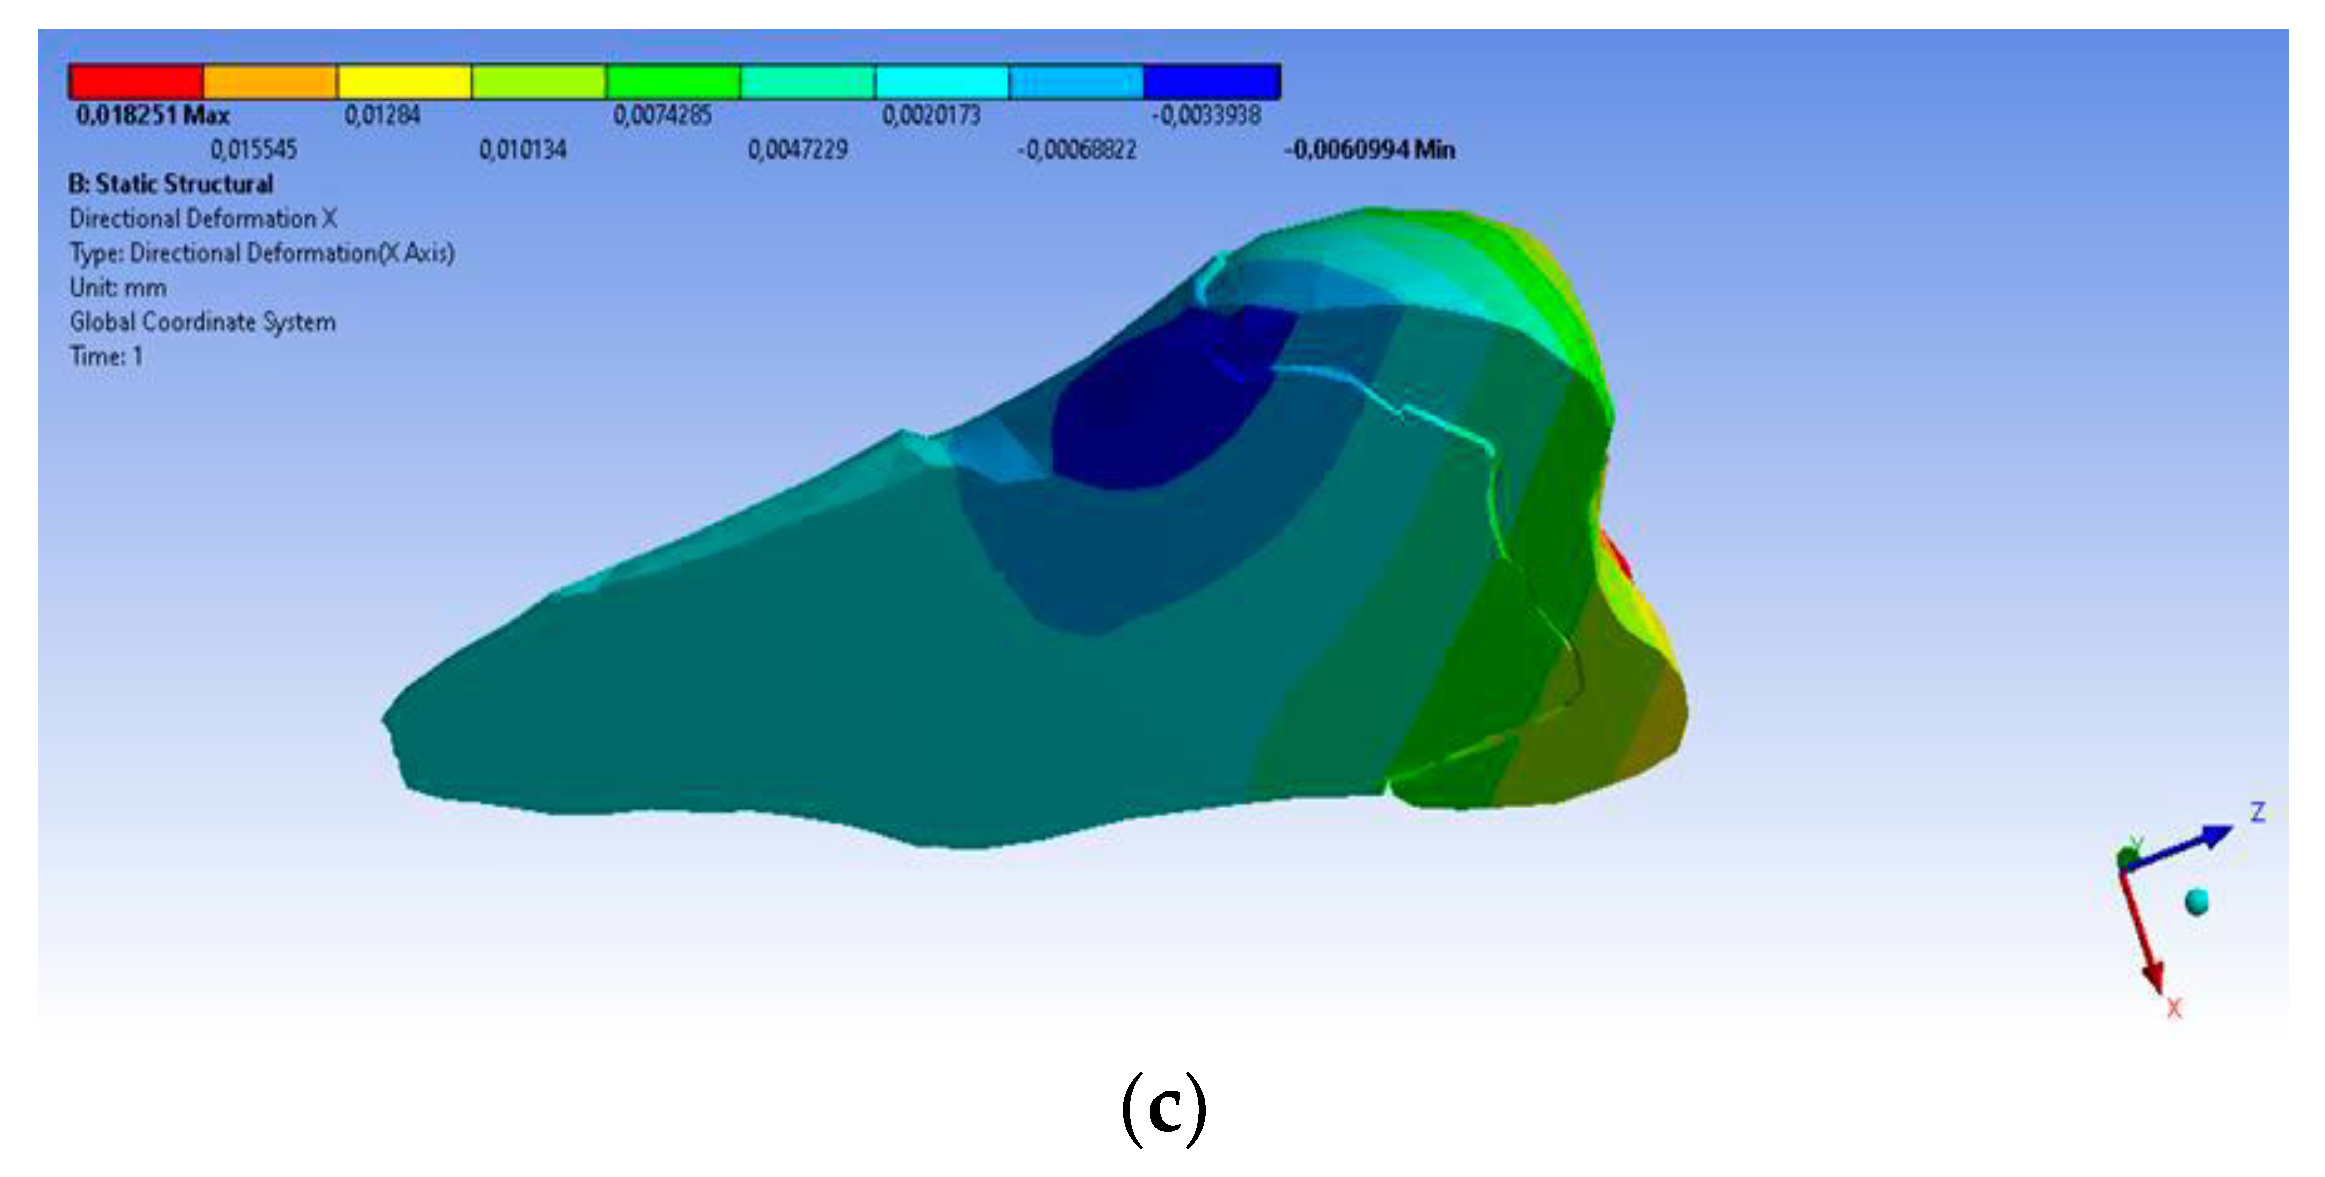

3. Finite Element Analysis (FEA) of Mandibular Right Premolars

| Minimum | 0 mm | −4.24 × 10−3 mm | −2.52 × 10−2 mm | −1.56 × 10−2 mm | 1.01 × 10−6 MPa | −35.6 MPa | −57.1 MPa | −104 MPa | −15.2 MPa | −152 MPa | −43.7 MPa | −39.6 MPa | −56.3 MPa |

| Maximum | 2.77 × 10−2 mm | 3.57 × 10−3 mm | 6.98 × 10−4 mm | 4.78 × 10−3 mm | 248 MPa | 61.5 MPa | 177 MPa | 72.2 MPa | 195 MPa | 21.4 MPa | 44.2 MPa | 117 MPa | 22.2 MPa |

| Minim. in | Cementum | Cementum | Enamel | Enamel | Cementum | Cementum | Enamel | Enamel | Enamel | Cementum | Enamel | Enamel | Cementum |

| Maxim. in | Enamel | Enamel | Cementum | Enamel | Cementum | Enamel | Enamel | Enamel | Enamel | Enamel | Cementum | Cementum | Cementum |